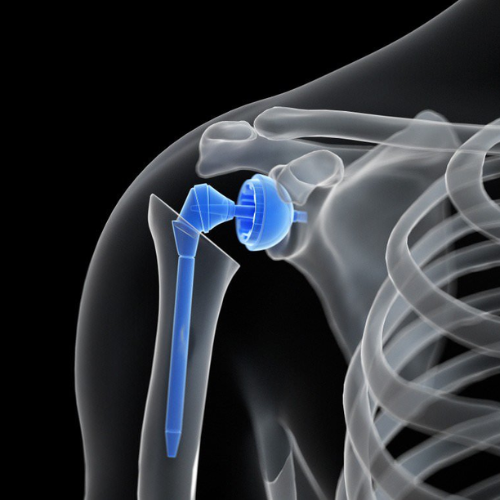

Arthroplasty is a surgical procedure that involves replacing a damaged joint with an artificial implant to restore mobility and eliminate pain. It is most commonly performed on weight-bearing joints like the knee, hip, and shoulder, especially when conservative treatments fail to provide relief.

• Shoulder Arthroplasty